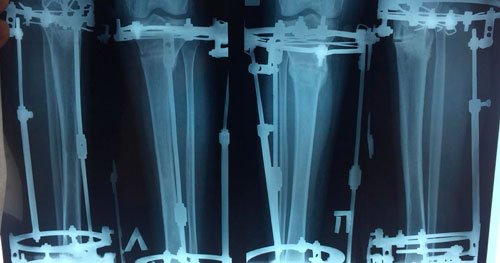

Дата операции - 04.03.2019г.

Дата снятия аппаратов - 03.06.2019г.

Срок сращения - 90 дней.